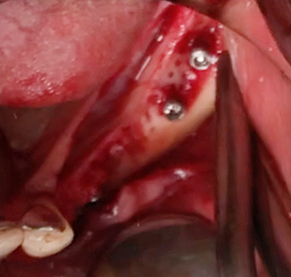

Simultaenous bone grafting for implants

Implants/Bone Grafting

Partial edentulous clinical cases